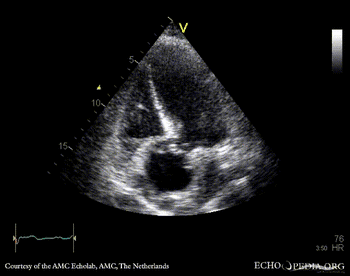

Aortic dissection type A

Suprasternal view: dissection flap in aortic arch Subcostal view: dissection flap in abdominal aorta